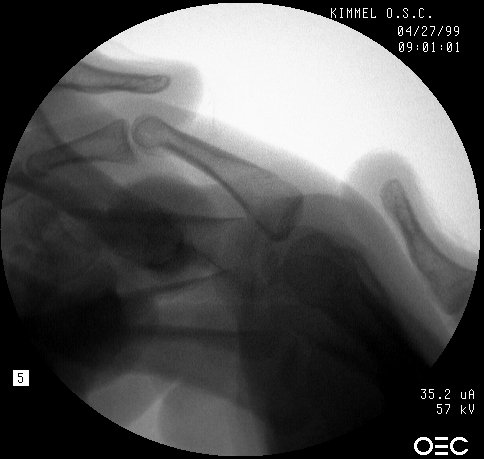

| Proximal phalanx fractures are a common problem with many treatment options. These images illustrate a technique of stabilization using intramedullary Herbert screws placed percutaneously through the base of the proximal phalanx. Provisional fixation is obtained with K wires which are replaced with Herbert screws, which simply follow the soft tissue path of the pin tract to the bone. Self tapping screws are not used in this technique, as the cutting threads catch on soft tissues. |

| One of the problems with completely displaced proximal phalanx fractures is a tendency to redisplace after temporary percutaneous pinning. This fracture was treated acutely. |